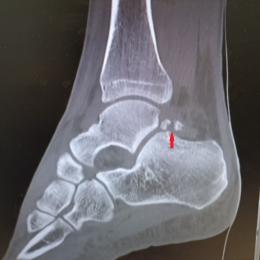

Fracture de l’os trigone

Miguel, 41 ans, consulte à la suite d’une chute mal réceptionnée dans le bassin d’un toboggan de parc aquatique. Depuis, il a une douleur...